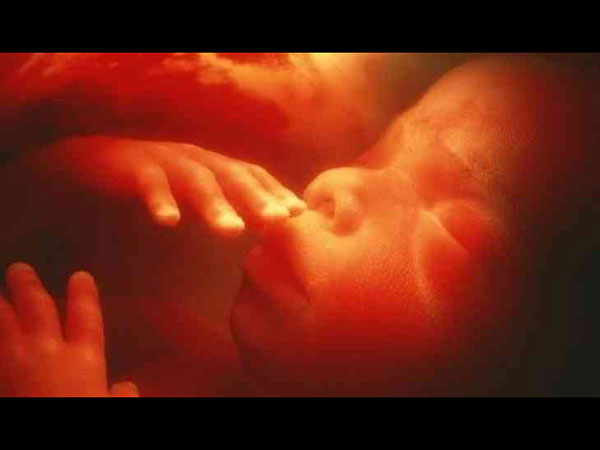

Unborn Baby Was Removed From Mum’s Womb For Surgery

With science making immense progress in everything, you would not be surprised to know how an unborn child underwent a surgery while it was still in the mother's womb!

The case has become medical history after its success. Check out the details of this case that makes us realise how advanced our science technology is!

The doctors offered the couple a new option called as foetal surgery where they would fix the unborn child's condition even before she is born. The surgery involved removing the unborn baby from the mother's womb and repairing the spinal cord of the child, so that the baby has greater chances of leading a normal life.

The Baby Was Later Put Back In The Womb

Doctors revealed that the baby was then later placed back in the mother's womb to complete the pregnancy term. The medics also revealed that the surgery was a success and revealed that people can opt for this surgery as studies revealed that about 80% of babies are terminated after their parents know about the baby's condition.